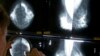

สำหรับวันมะเร็งโลกในปีนี้ ทางองค์การอนามัยโลกได้เน้นความสำคัญของการตรวจพบมะเร็งแต่เนิ่นๆ และชี้ว่าผู้ป่วยที่ตรวจพบมะเร็งเเต่เนิ่นๆ และได้รับการบำบัดรักษาทันที จะมีโอกาสที่สูงขึ้นในการรักษาให้หาย

โดยเฉพาะคนที่เป็นมะเร็งทรวงอก มะเร็งปากมดลูก และมะเร็งลำไส้ใหญ่